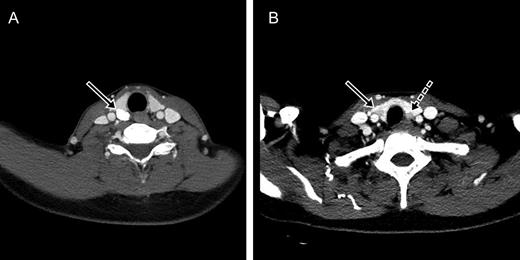

Parathyroid glands and the thyroid nodule on computed tomography. (A) A calcified nodule posterior to the right superior thyroid (arrow). (B) A solid nodule in the right lower thyroid gland (arrow) and an enlarged parathyroid gland posterior to the left inferior thyroid (dotted arrow).